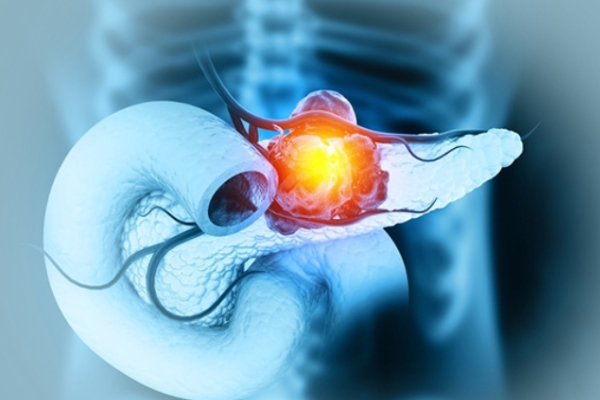

سرطان پانکراس یکی از مرگبار ترین انواع سرطانهای دستگاه گوارش محسوب میشود. پانکراس یا لوزالمعده یک غده حیاتی در بدن است که در قسمت فوقانی شکم، پشت معده قرار دارد و نقش مهمی در هضم غذا و تنظیم قند خون ایفا میکند. این عضو از طریق تولید آنزیمهای گوارشی و هورمونهایی مانند انسولین، عملکرد متابولیکی بدن را تنظیم میکند. وقتی سلولهای پانکراس به صورت غیرطبیعی شروع به رشد و تقسیم میکنند و توده ای سرطانی شکل میگیرد، به آن سرطان پانکراس میگوییم.

سرطان پانکراس اغلب به دلیل رشد آهسته و بروز دیرهنگام علائم، در مراحل پیشرفته تشخیص داده میشود. به همین دلیل، شناخت زودهنگام علائم و عوامل خطر این بیماری از اهمیت بالایی برخوردار است.